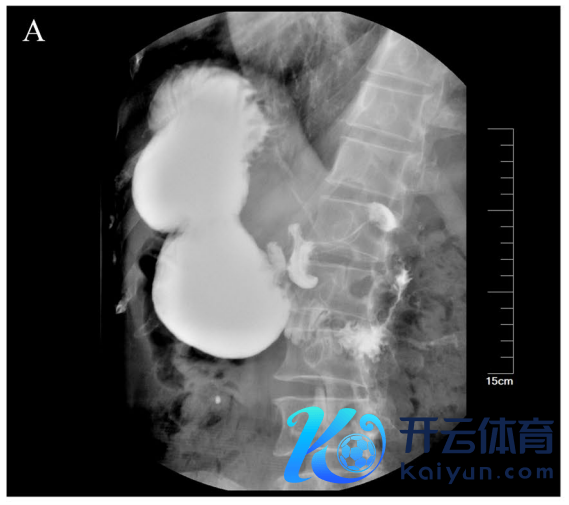

钡剂造影:胃体积增多、胃潴留、胃肠吻合口狭隘,造影剂通过受阻(图1A)。

图1A. 术前上消化谈x线钡餐示胃潴留,胃十二指肠吻合口狭隘,造影剂通谈梗阻。